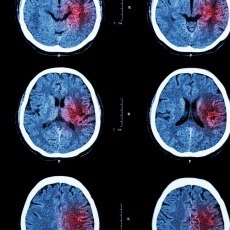

An ischemic stroke happens when a blood clot blocks a blood vessel in the brain, cutting off oxygen and nutrients. It is the most common type of stroke and can cause brain damage, disability, or death if not treated quickly. Causes include blood clots (thrombosis or embolism), atherosclerosis (plaque build-up), irregular heart rhythms (like atrial fibrillation), and other heart or blood disorders. A TIA (mini-stroke) is a brief blockage that increases future stroke risk. Symptoms appear suddenly and may include numbness or weakness (especially on one side), confusion, trouble speaking or seeing, dizziness, loss of coordination, and severe headache. The F.A.S.T. test helps identify stroke: Face drooping, Arm weakness, Speech difficulty, Time to call 911. Diagnosis involves physical exam, medical history, imaging tests, and heart evaluations. Treatment includes clot-busting drugs (thrombolytics), blood thinners, surgery or stenting for narrowed arteries, and rehabilitation to regain lost functions. Medicines may also manage risk factors like high blood pressure, cholesterol, or diabetes. Prevention focuses on heart-healthy lifestyle changes (diet, exercise, quitting smoking) and medications if needed.